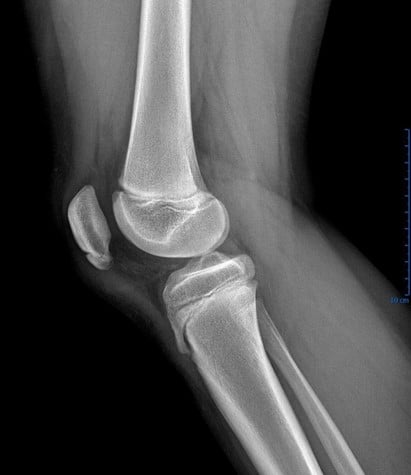

Bipartite or Multipartite Patella

This is a subtle bipartite patella with lateral abnormality

Case courtesy of Dr. Sumit Verma, Radiopaedia.org. From the case rID: 74103

Case courtesy of Dr. Aditya Shetty, Radiopaedia.org. From the case rID: 27156